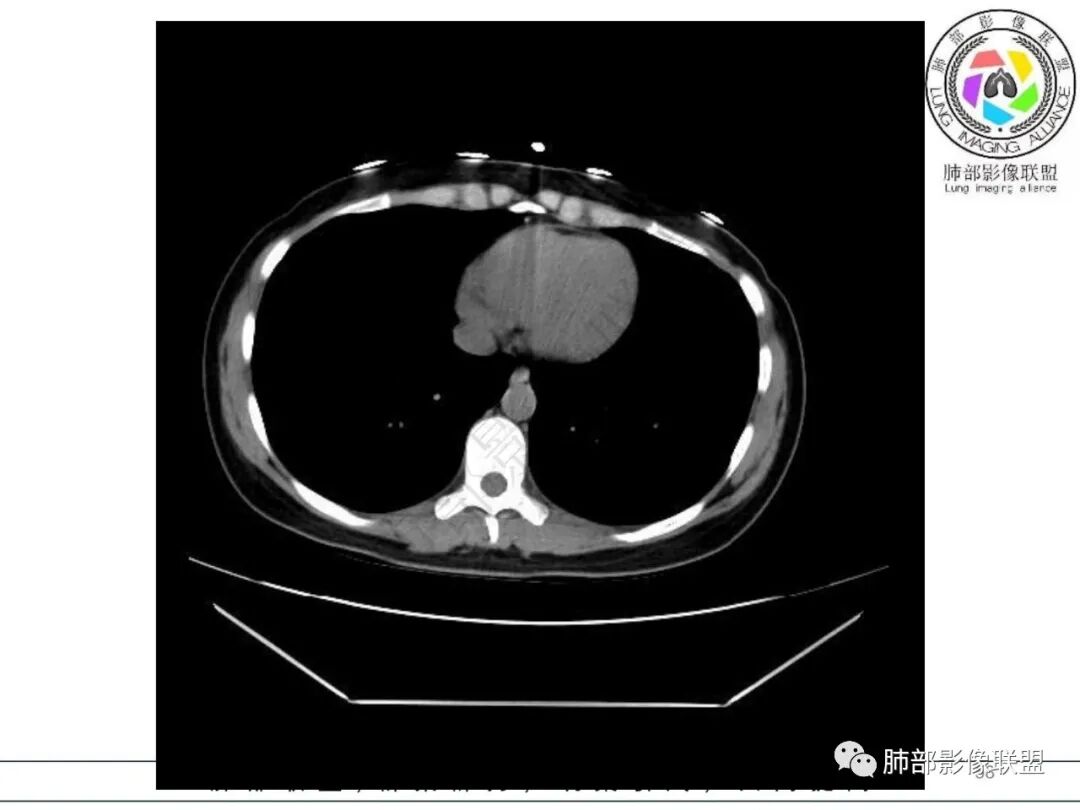

2.影像特征:右肺下叶局限性实变影伴晕征,边界不清,内部支气管尚通畅,实变区密实区边缘稍膨隆。符合炎性病灶特征。

3.综合分析:急性病程,炎性指标高,常见的是普通社区肺炎,如肺炎链球菌感染等。但本例患者临床表现较重,应先表现相对较轻,白细胞不高,须考虑非典型肺炎的可能性。本例隐球菌荚膜实验阴性,而军团菌临床症状一般较重,影像分布也更广泛、进展迅速,多器官损害更明显。因此考虑鹦鹉热衣原体可能性更大一些。其他如腺病毒等感染也是需要排除的。

最终支气管镜灌洗NGS确诊为鹦鹉热衣原体感染。